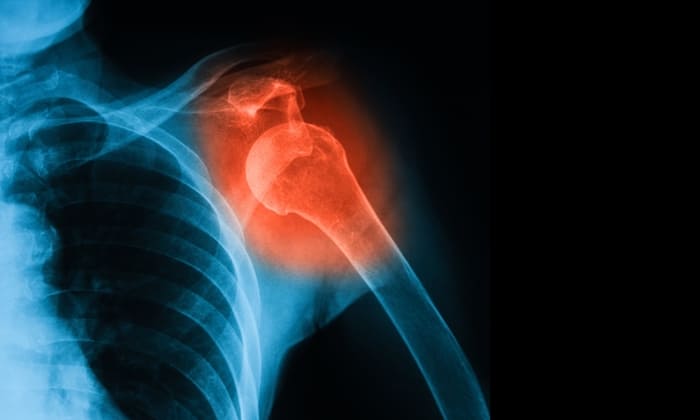

ข้อเคลื่อน หรือข้อหลุด (Dislocation of joint หรือ Dislocation) คือ ภาวะที่หัวกระดูกหรือปลายกระดูกสองอัน ที่มาชนกันเป็นข้อ เคลื่อนหรือหลุดออกจากตำแหน่งปกติ จนส่งผลกระทบต่อเนื้อเยื่อ เส้นเอ็น กล้ามเนื้อ เส้นเลือด และเส้นประสาทในบริเวณนั้น เช่น ทำให้ฉีกขาด ฟกช้ำ ยืด

ข้อเคลื่อน (Dislocation)

ข้อเคลื่อนส่วนมากเกิดบริเวณหัวไหล่ และนิ้วมือ ส่วนอื่นที่มักเกิดข้อเคลื่อน เช่น ข้อศอก หัวเข่า สะโพก ส่วนใหญ่แล้ว หากข้อบริเวณใดเคยเกิดภาวะข้อเคลื่อนแล้ว ก็สามารถกลับมาเป็นซ้ำได้ในอนาคต

• เอกซ์เรย์ ตรวจเช็คจุดที่ข้อเคลื่อน และการแตกหักอื่น หรือส่วนที่บาดเจ็บของข้อต่อ